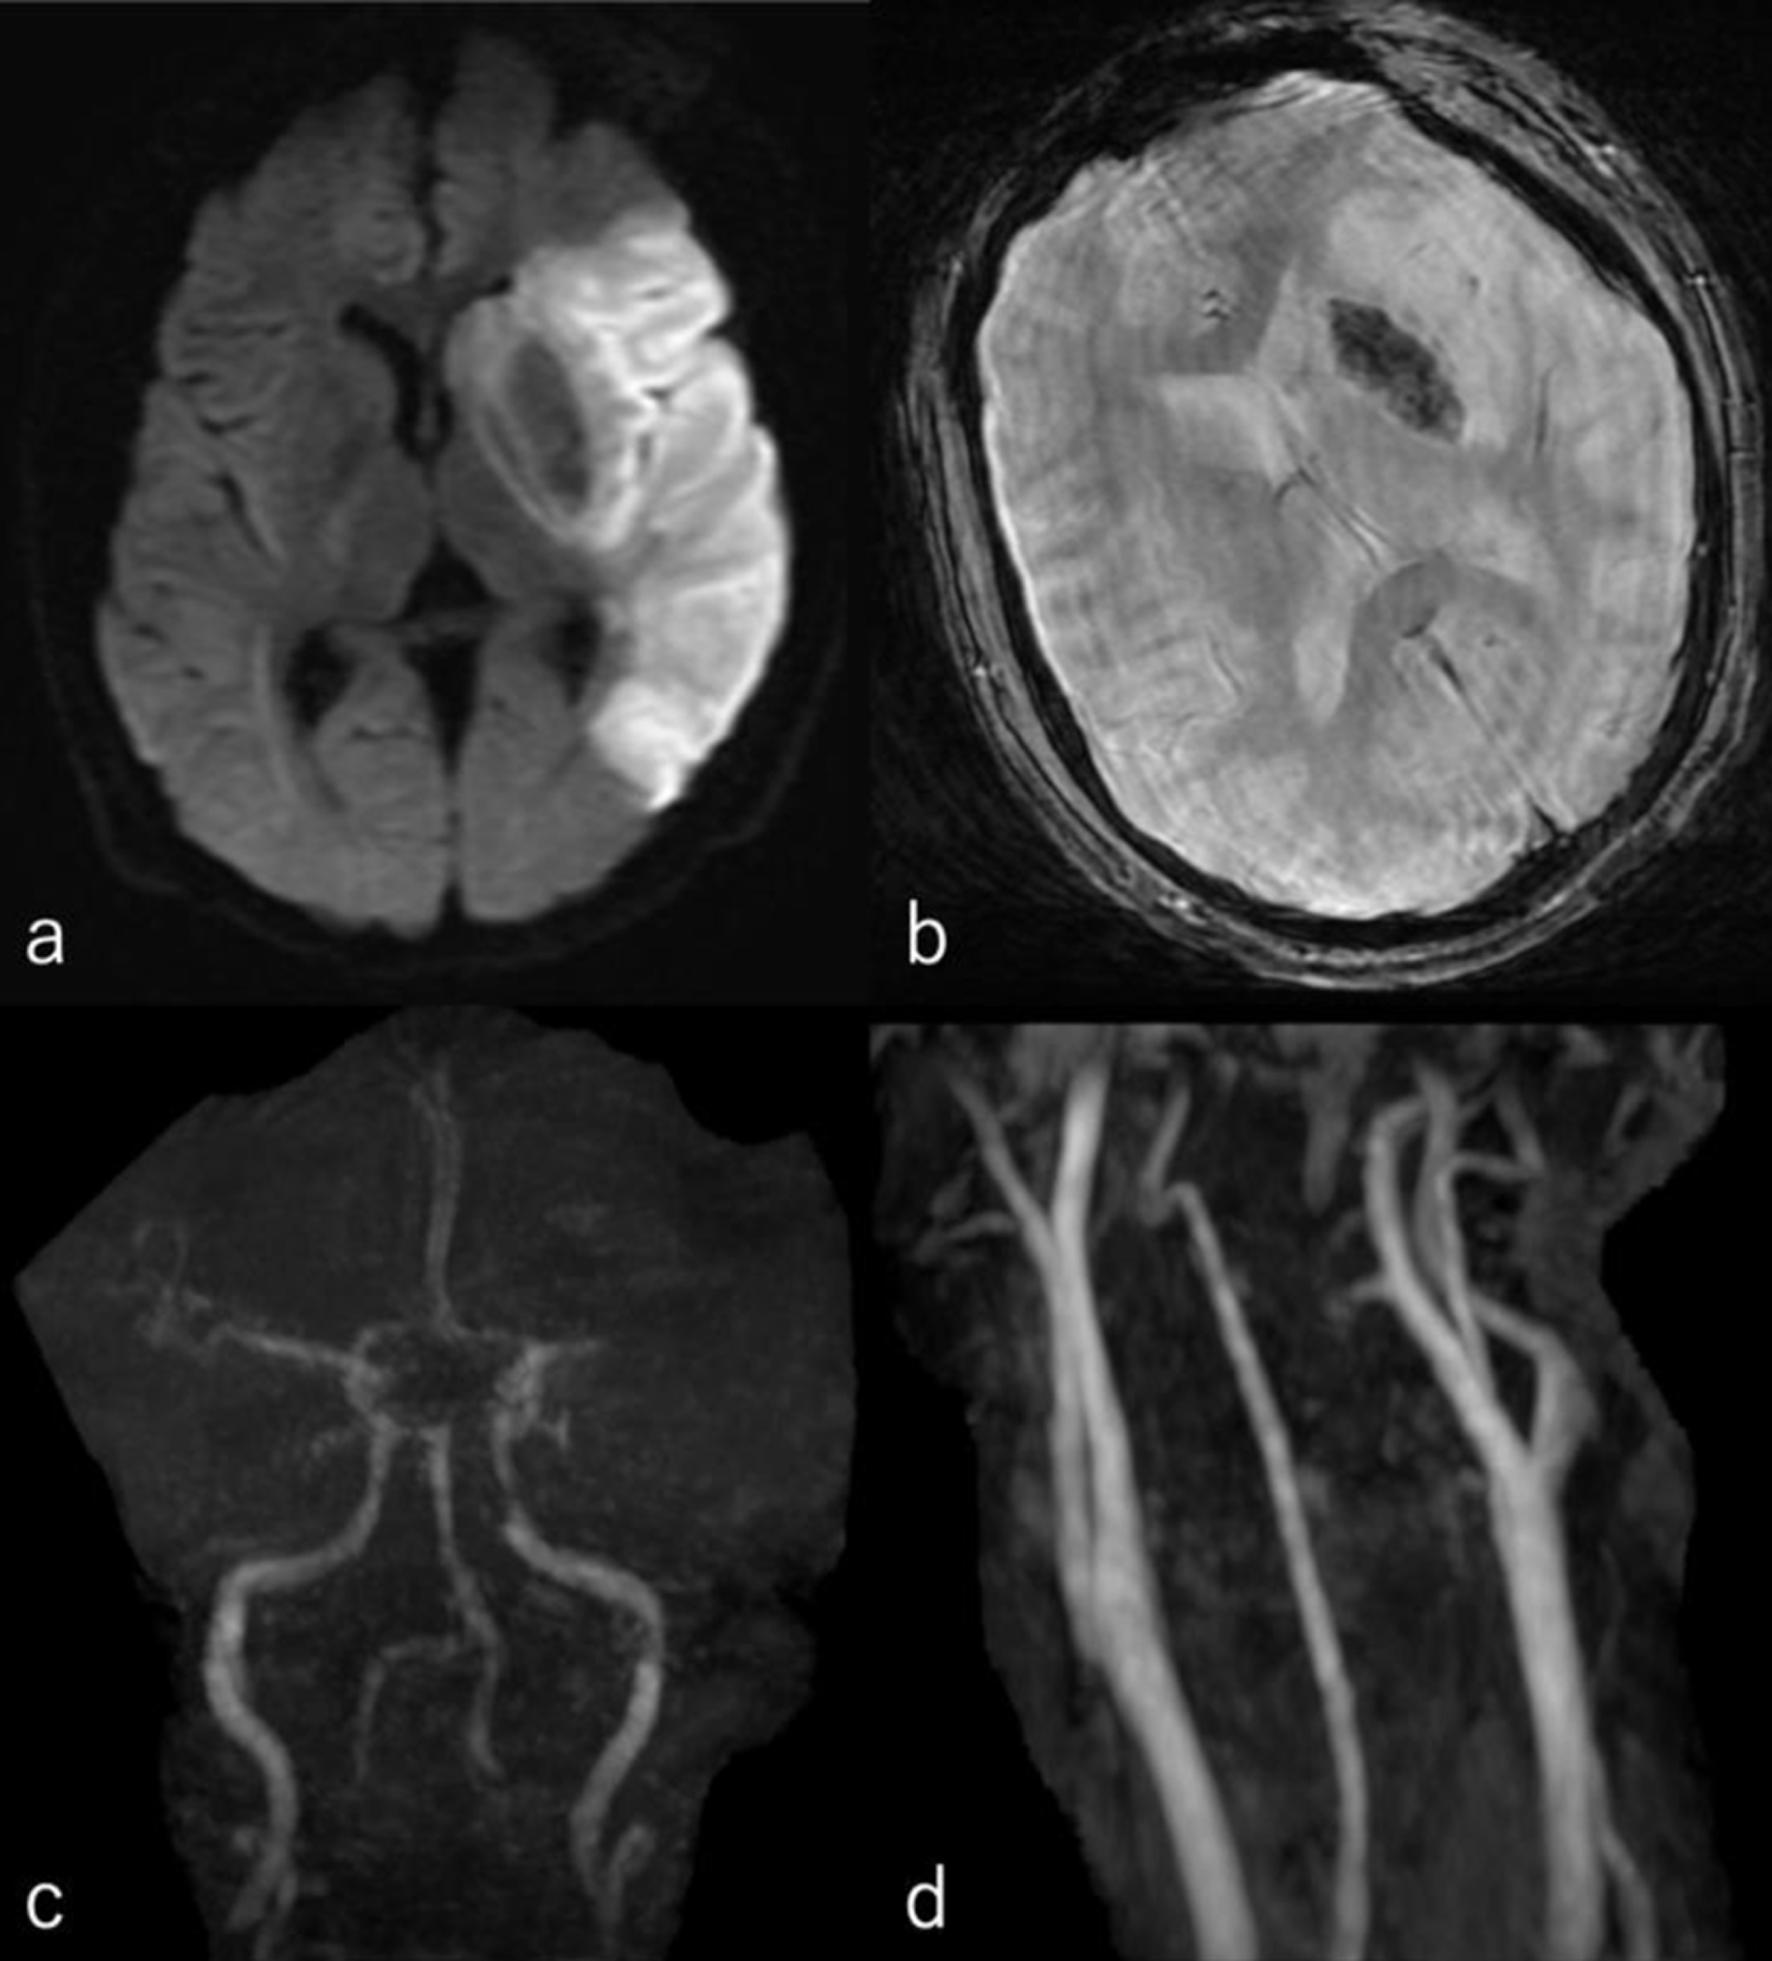

The following day, no apparent hemorrhagic extension was observed. On carotid artery ultrasonography, there was a mobile lesion at the origin of the left ICA (Fig. 2). Further examination with three-dimensional computed tomography angiography (3D-CTA) revealed the presence of irregular contrast in the posterolateral wall of the left cervical ICA origin (Fig. 3a-d). MRI plaque image revealed a structure that was T1 isointense (Fig. 4a) and T2 high intense (Fig. 4b) with the vessel wall, protruding into the lumen (Fig. 4). On the second day, cerebral angiography revealed a shelf-like structure on the posterior wall of the left ICA origin (Fig. 5a), and the left MCA was recanalized. Cerebral angiography revealed pooling of blood flow on the rostral side of the lesion (Fig. 5b).

Figure 5. (a) Cerebral angiography revealed a shelf-like structure on the posterior wall of the left internal carotid artery origin on the second day. (b) Cerebral angiography revealed pooling of blood flow on the rostral side of the lesion.